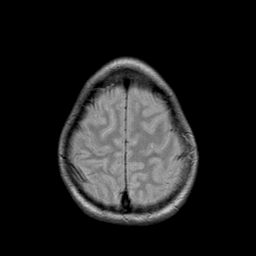

Metastatic bronchogenic carcinoma: proton density-weighted MR -- Slice #19

[Home][Help][Clinical] Slice 19